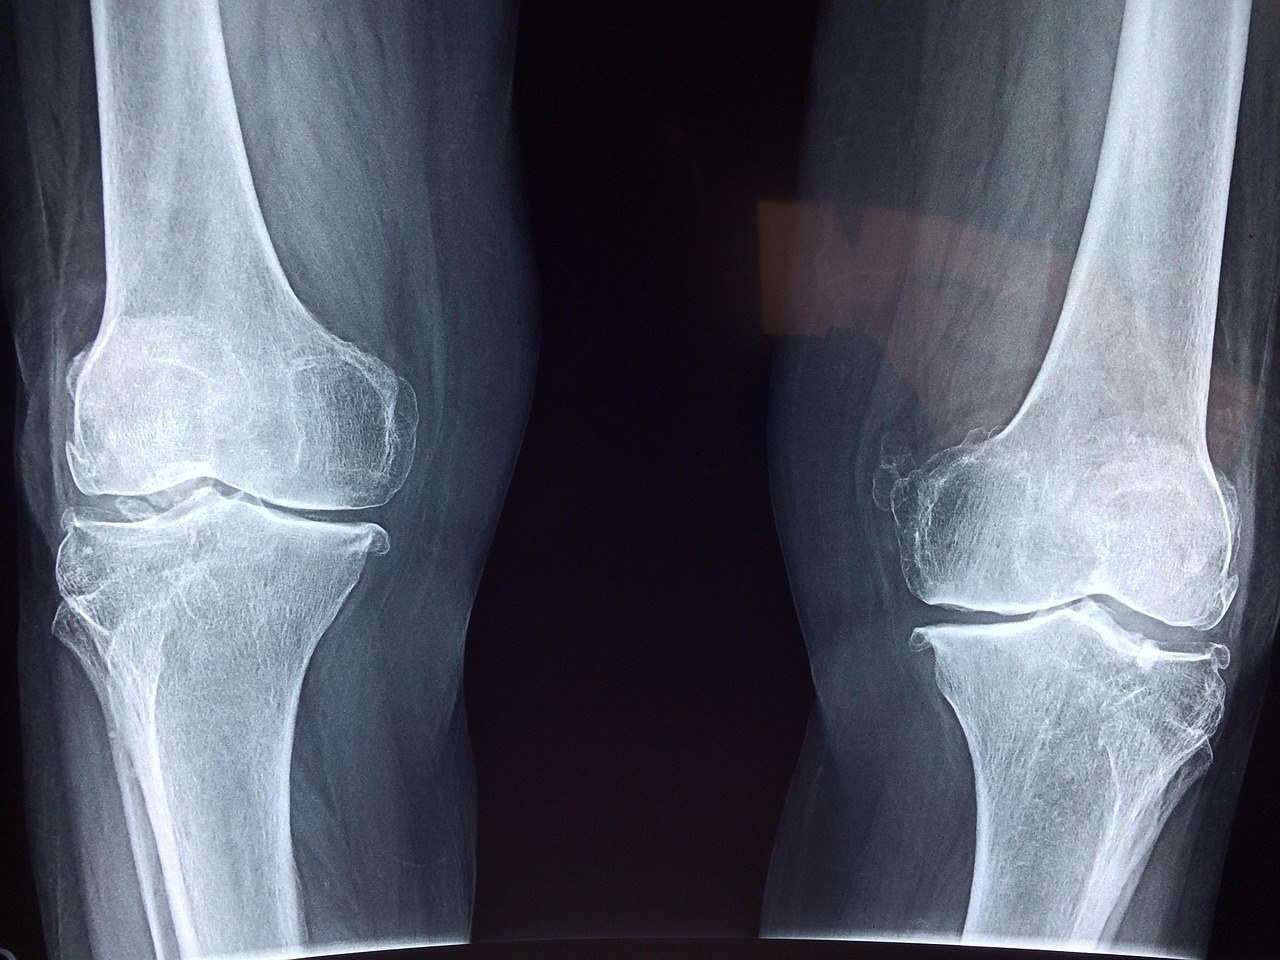

Investigating the physiological mechanics of joints unveils secrets about movement efficiency and adaptability. The mechanics of how joints operate involve not just the bones but also muscles, tendons, and ligaments. Each element plays a crucial role in facilitating smooth motion and ensuring joint stability. Take, for instance, the intricate structure of the human knee joint, where ligaments prevent excessive movement and stabilize the joint during complex movements. Gait analysis in humans exemplifies how understanding joint mechanics aids in addressing movement deficiencies and developing rehabilitation techniques. Similarly, in animals, understanding joint mechanics helps optimize their natural movements. By studying various species, researchers can explore how differences in joint mechanics affect speed, agility, and endurance. This knowledge is vital for sports medicine and improving athletic performance. For instance, it explains why some terrestrial mammals excel in sprinting while others are better adapted for endurance. As comparative anatomy evolves with technological advancements, the potential for new insights into joint mechanics and their applications expands considerably. Overall, understanding joint mechanics enhances our knowledge of mobility within the animal kingdom.

Clinical implications of joint study extend into veterinary medicine, biomechanics, and rehabilitation sciences. Understanding the anatomy and mechanics of joints is crucial for diagnosing and treating joint-related disorders in various species, including humans. Conditions such as osteoarthritis significantly affect joint function, necessitating advanced knowledge of joint structure for effective management strategies. Insights gained from comparative anatomy guide both clinical practices and surgical interventions. For instance, techniques developed for human joint replacements have roots in studies of joint anatomy across different animals. Moreover, the understanding of ligaments and cartilage health is vital in sports medicine, where joint injuries can impact performance. By examining joint adaptations among species, veterinarians and healthcare professionals can devise innovative treatments that enhance recovery. Furthermore, biomechanics research continuously informs us how various species utilize their joints efficiently in movement. This information can influence training regimens, prevent injuries, and improve performance in both human athletes and working animals. Therefore, a comprehensive grasp of joint anatomy is invaluable across a spectrum of disciplines, paving the way for advancements in healthcare and performance optimization.